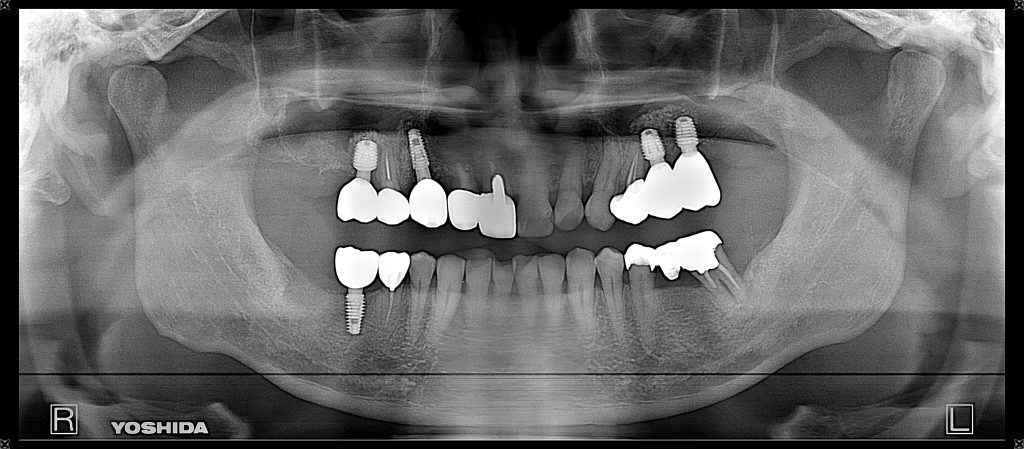

症例140代 男性 主訴 左右臼歯部欠損の為、奥歯で噛めない 前歯がグラつく

治療前

治療後

奥歯でしっかり噛めるようにインプラントを計画・提案。

前歯の長いブリッジは力学的に負担がある為、支えとなるインプラントを配置。

右上小・大臼歯部は、骨高不足の為、ソケットリフト(上顎洞洞底膜挙上術)を適用。

約5ヶ月間の治療期間を経て、全てジルコニアを装着し終了。

リスクとしては外科的侵襲がある。デメリットは、保険外診療の為、経済的負担がある。

費用 340万(税込)(オペ・仮歯・最終補綴物まで含む)